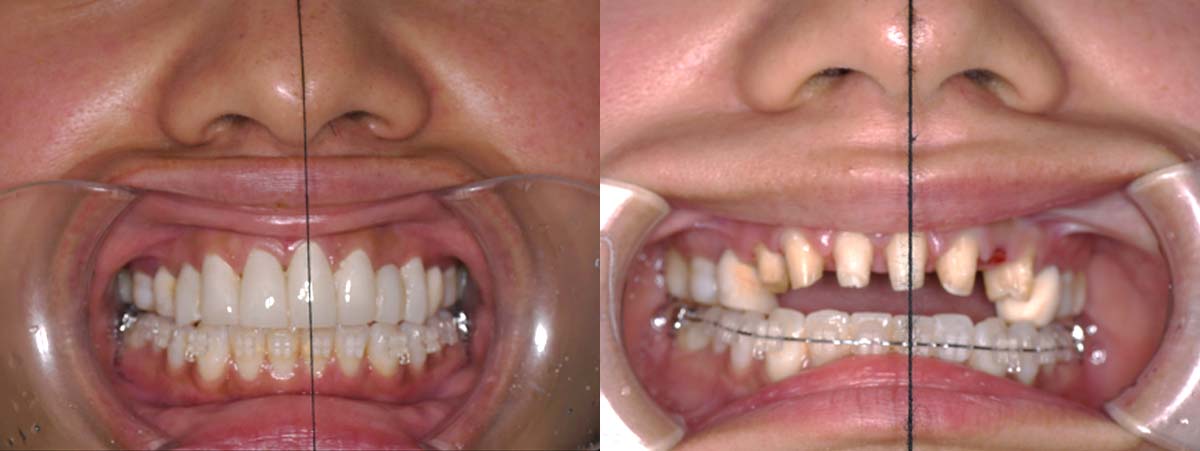

2024年 10月 下顎MTM開始

2024年 10月10日